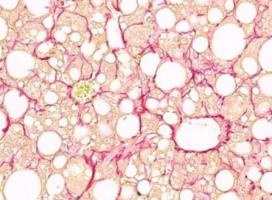

Actualité publiée le 03/11/2021De la STÉATOSE HÉPATIQUE à la stéatohépatite non alcoolique, quels mécanismes ?

Actualité publiée le 08/02/2021FOIE GRAS : Objectif exercice plutôt que perte de poids ?

Actualité publiée le 17/08/2020